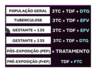

Tratamento

nunca é emergência médica , exceto (2)

acidente ocupacional e violência sexual

Tratamento

Por que não parar a medicação quando carga fica indetectável (1)

evitar seleção

Tratamento

maioria dos soropositivos vai usar no mínimo 3 drogas

verdadeiro

TDF, 3TC, DTG

Tratamento (V ou F)

todos soropositivos vão fazer TARV

verdadeiro

Tratamento

objetivo

carga viral indetectável em até 12 meses de tratamento